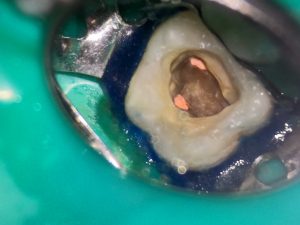

![]() Відкриття пошкодженого зуба

![]() Видалення інфекції з коронкової частини зуба ( повне прибирання карієсу)

![]() Механічна обробка кореневих каналів

Пацієнт звернулась у клініку із скаргами на погану пломбу. При огляді КЛКТ виявлено апікальний періодонтит на медіально-щічному корені, причиною якого є невдале минуле лікування кореневих каналів. В один візит проведено, під місцевою анестезією, видалення старої пломби, відновлення зруйнованої стінки, розпломбування кореневих каналів, які були запломбовані резорцин-формаліновим цементом. Пломбування кореневих каналів проведено біокерамічним силлером та гутаперчею. В цей же візит зуб відновленно фотополімерним матеріалом. Після лікування зуба пацієнт направлений до ЛОР хірурга на видалення міцитоми з гайморової пазухи.